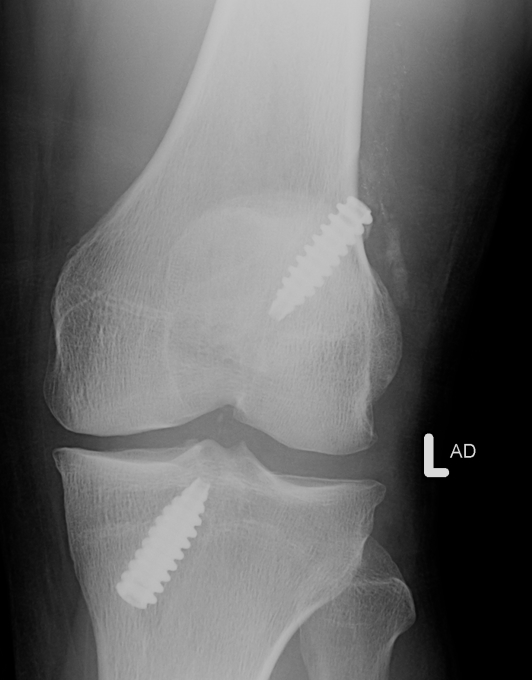

Secure

- insert femoral screw outside in

- tension tibial side

- must not overtension as there is no give in the graft

- secure tibial side with screw